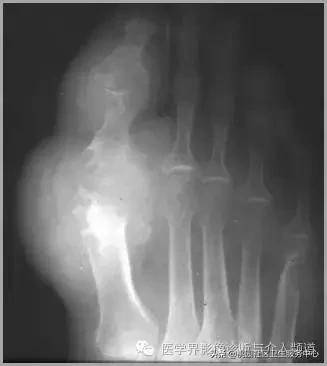

4、痛风石

为尿酸盐沉积形成,发生在关节周围软组织、包括韧带、肌腱、滑囊,眼、耳、鼻、喉、皮肤, 50%的钙化为X线平片可见。

痛风石,可见软组织肿胀及钙化灶。